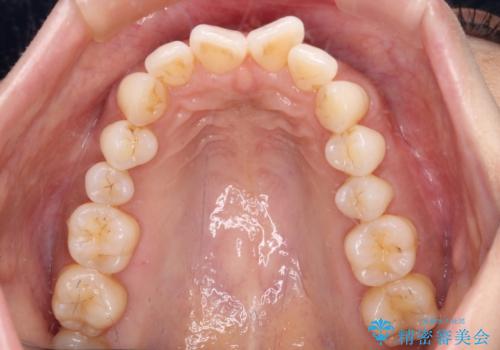

- 前歯の突出感とデコボコを気にして来院された患者様です。

奥歯の噛み合わせをみると、上顎歯列が全体的に前突している状態であり、この咬み合わせのまま歯列を整えると出っ歯になってしまう可能性がありました。

アンカースクリューと補助装置を使用して上顎大臼歯を遠心移動させることで咬み合わせを改善し、ワイヤー装置によりデコボコを解消しながら口元の突出感も改善していくこととしました。

出っ歯になることなく、上下前歯が綺麗に接触する状態で仕上げることができました。